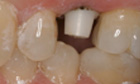

Before and After Pictures

The above images demonstrate the sequence of events for replacing a single missing tooth with a dental implant. The implant fixture is placed and allowed to heal, then a post or abutment is seated, and then a final crown is placed on top.